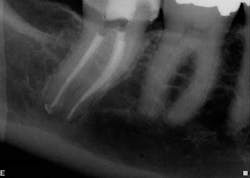

For example, in canal anatomy that appears to be fairly straight on preoperative radiographs in roots with traditional taper, a single file system such as WaveOne(Dentsply Tulsa Dental Specialties) would be an excellent choice to achieve cleanliness and shape (Figs. 1 and 2). The single-file reciprocating system would also have the added benefits of simplicity and efficiency.

In these three cases, different instrumentation systems were used to create the final shape of the root canal system. In spite of differences in the number of files used, the file design and file movement, the end results look very similar. Although potentially confusing to clinicians, the advances in metallurgy and file design allow for safer and more efficient cleaning and shaping of the root canal system than ever before. However, despite these advances, the success rates of endodontic treatment have stagnated over the last several decades, indicating there is more to clinical success than a dense, white line on a radiograph. Canal shaping is important, but it is paramount that an effective irrigation protocol is incorporated into the endodontic procedure to safely and effectively eliminate all possible bacteria.Fig. 1: Although access is usually an issue when treating second molars, the shape of the roots and good chamber size suggest WaveOne would be an ideal file system for tooth No. 2.

Fig. 2: Following establishment of a glide path and removing the dentin triangle, a single WaveOne primary file was used to create the final shape. This shape would allow for deep and safe delivery of irrigants and maximum disruption of biofilm.